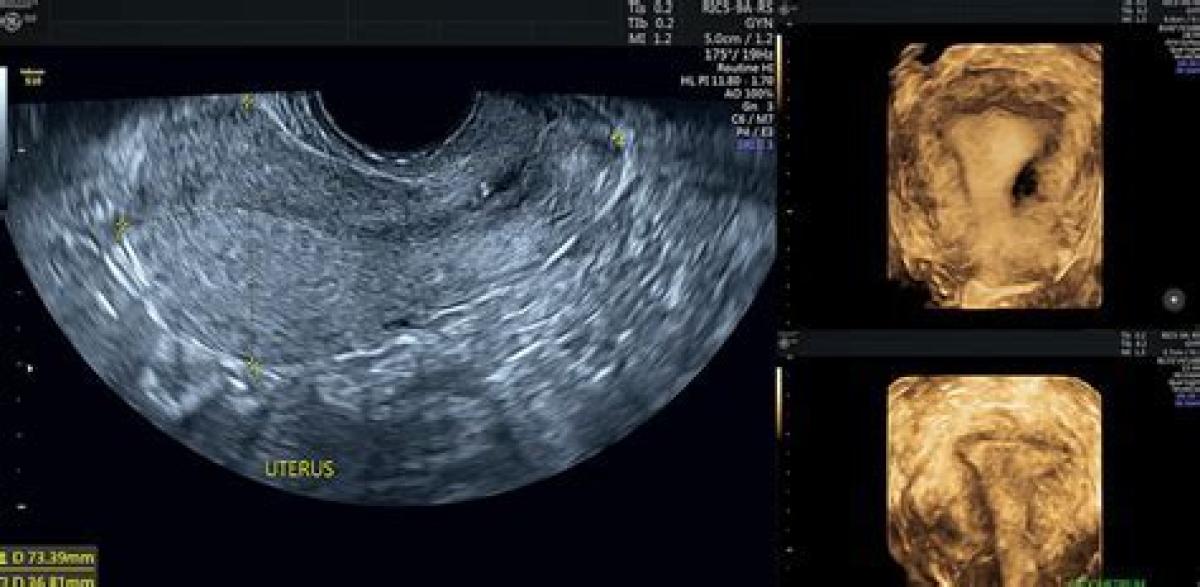

سونوگرافی ترانس واژینال TVS, یکی از انواع سونوگرافی هایی است که برای زنان و مادران باردار تجویز می شود. این سونوگرافی که از طریق واژینال انجام می شود, دقت بسیار بالایی در تشخیص دارد و به پزشک کمک می کند تا تشخیص بهتری از بیماری و یا سلامت بیمار داشته باشد. سونوگرافی ترانس واژینال با استفاده از امواج صوتی با فرکانس بالا, تصاویری از قسمت های داخلی بدن ایجاد می کند و نشان می دهد. هر چند سونوگرافی های شکمی دقیق هستند و اطلاعات دقیقی از قسمت های داخلی شکم را نشان می دهند اما در مورد ارگان های لگنی زیاد دقیق عمل نمی کند و بهترین پیشنهاد برای بررسی ارگان های لگنی, استفاده از ترانس واژینال است.

درسونوگرافی ترانس واژینال برخلاف سونوگرافی عادی شکمی که مبدل بر روی شکم قرارمی گیرد, پزشک مربوطه پروب سونوگرافی که حدودا ۲ یا ۳ اینچ است, داخل کانال واژن قرار می دهد. پزشکان از این سونوگرافی برای بررسی اندام های تولید مثل زنان مانند تخمدان, رحم, دهانه ی رحم, لوله های فالوپ و مثانه استفاده می کنند. چرا که این اندام ها از طریق واژن به راحتی قابل مشاهده است.